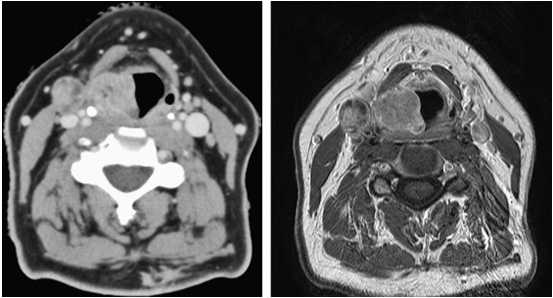

(Слева) При аксиальной КТ с КУ в преддверии гортани визуализируется объемное образование, смещающее жировую ткань. Его часть, не накапливающая контраст и имеющая плотность, соответствующую слизистому компоненту, представляет собой внутреннее ларингоцеле, возникшее в результате обструкции желудочка гортани опухолью.

(Справа) При аксиальной КТ с КУ у этого же пациента, выполненной каудальнее, визуализируется опухоль (плоскоклеточный рак), полностью вовлекающая окологортанное пространство. Пластинка щитовидного хряща склерозирована, но признаков ее деструкции нет. Подподъязычные мышцы ниже уровня подъязычной кости слева не выглядят измененными, признаков распространения опухоли за пределы гортани не выявлено (стадия Т3).в) Дифференциальная диагностика плоскоклеточного рака преддверия гортани: